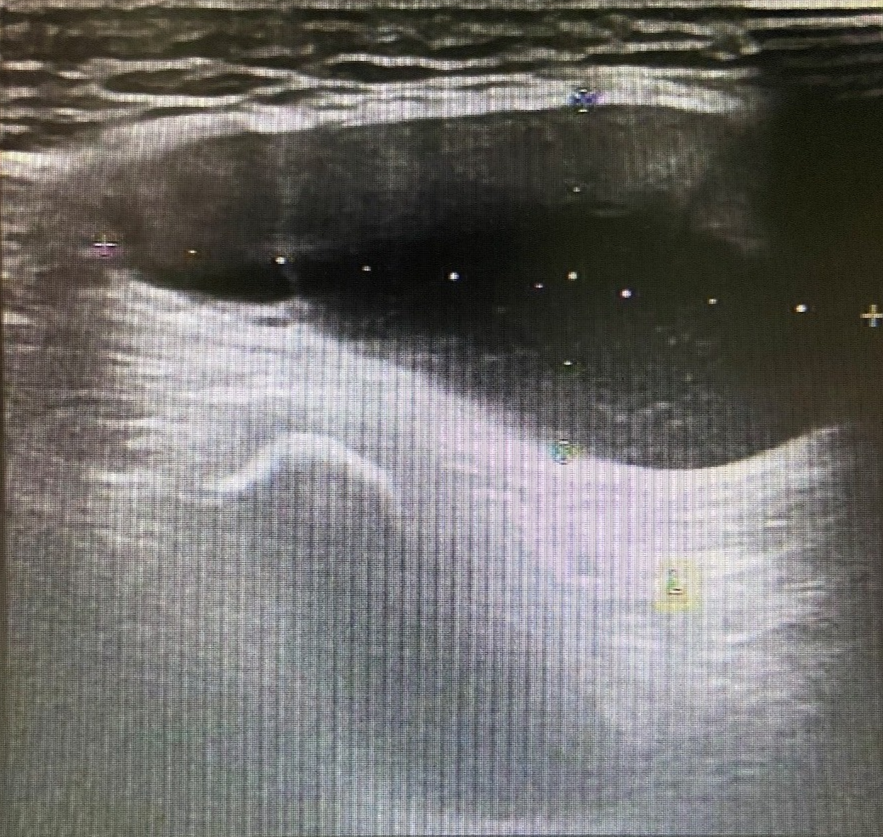

图片

图 3 左侧腹股沟区包块

超声所见

左侧腹股沟区见范围约 4.4cm×3.2cm×2.0cm 无回声区,可见少量分隔,增减腹压大小无明显变化。右侧腹股沟区未见明显异常回声。

超声提示

左侧腹股沟无回声区,子宫圆韧带囊肿?积液?

术后证实为左侧子宫圆韧带囊肿。